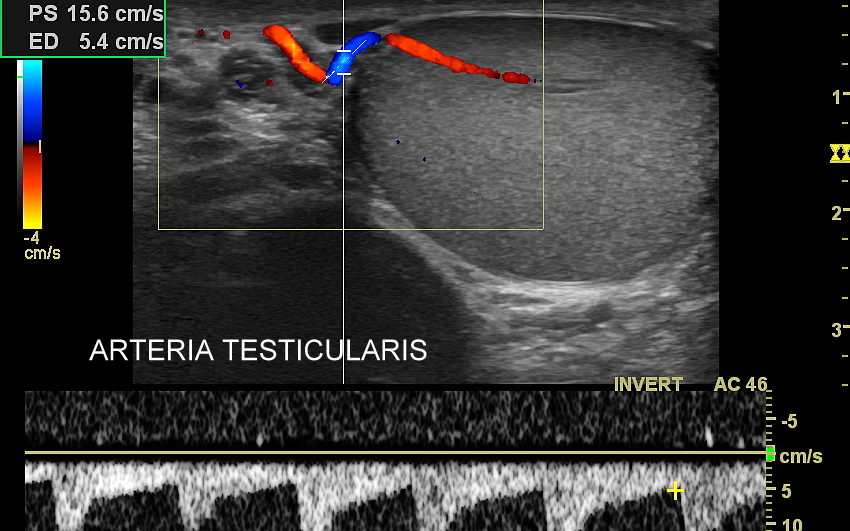

USG moszny i kanału pachwinowego jest podstawową metodą obrazowania jąder, najądrzy, powrózka nasiennego, w tym nasieniowodu oraz towarzyszących im naczyń żylnych i tętniczych. Badanie USG przeprowadzić należy w przypadku wystąpienia bólu i obrzęku jąder, pojawienia się macalnego guzka w obrębie moszny, podejrzenia skrętu lub zapalenia jądra, żylaków powrózka nasiennego, w ramach oceny dojrzewania płciowego chłopców. Kanał pachwinowy bada się także w sytuacji podejrzenia wnętrostwa, przepukliny pachwinowej, w celu oceny węzłów chłonnych, a także nasieniowodu w diagnostyce niepłodności męskiej.

Mosznę bada się aparatem USG wyposażonym w dedykowaną sondę o wysokiej rozdzielczości przeznaczoną do oceny jąder i drobnych struktur moszny, koniecznie z zastosowaniem trybów dopplerowskich, takich jak Doppler kodowany kolorem, Doppler spektralny i obrazowanie mikrounaczynienia. Dopełnieniem badania USG jąder jest użycie w stosownych przypadkach trybu elastografii oraz trybu USG z kontrastem (CEUS). Lekarzem, który pierwszy we Wrocławiu i na Dolnym Śląsku przeprowadził badanie CEUS jąder jest dr Tomasz Szczepański.